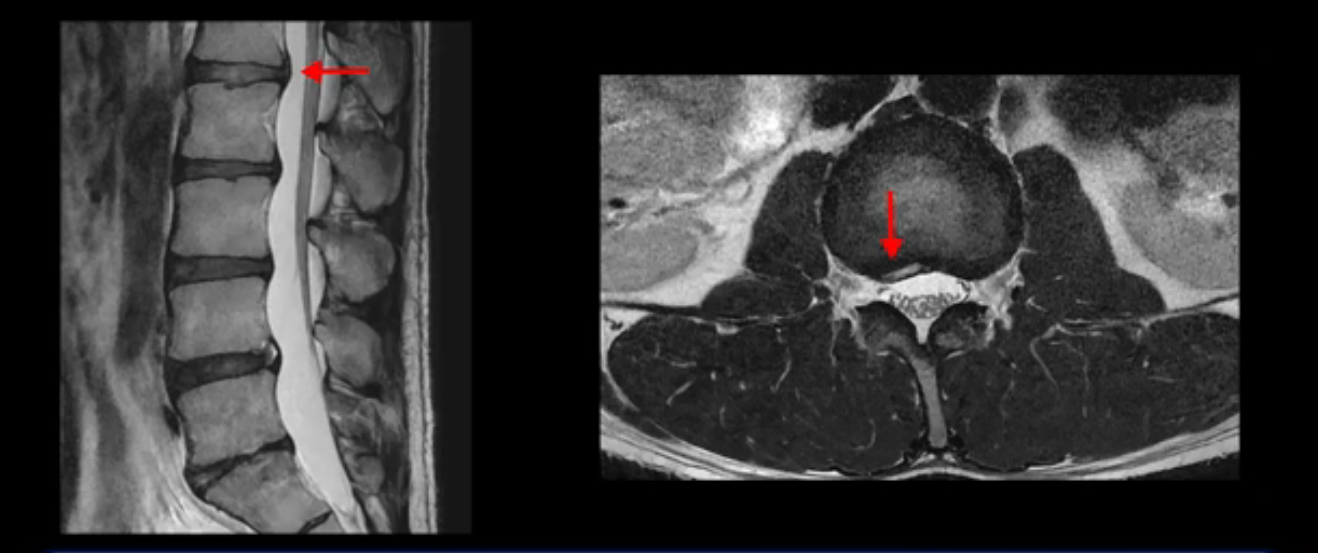

그런데 이분의 증상과 MRI가 전혀 일치하지 않는데, 왜 그런지 지금부터 자세히 설명드립니다. 이분 증상은 앉으면 엉치와 허리가 심하게 아파 10분 이상 앉는 게 어렵고 양쪽 발가락이 앉아있을 때나 누워있을 때 다 저립니다. 걸을 때도 아파서 10분 걷기도 어렵습니다. MRI를 마디마디 살펴보면 1번 2번은 오른쪽으로 살짝 밀려나온 디스크가 있지만 전혀 심하지 않고, 뒤에 또 설명하겠지만 최근에 밀려나온 급성 디스크가 아니고 오래된 디스크로 판단됩니다.

5번 1번 역시 가운데로 디스크 조금 밀려 나와있지만 신경 공간 넓이는 아주 넓어서 신경 눌림 있을 거라고 예상이 안됩니다.

추간공도 보시다시피 왼쪽, 오른쪽 전부 다 매우 넓어서 신경이 눌릴만한 부분이 전혀 보이지 않습니다.

앞서 1번 2번, 4번 5번, 5번 1번의 디스크가 찢어지고 조금 밀려 나온 게 최근에 찢어진 게 아니고 오래된 걸로 보인다고 말씀 드렸죠. 왜 그럴까요? 만약 급성으로 찢어진 것이라면 아주 심한 디스크성 통증이 있겠죠. 기침이나 재채기를 하면 심하게 아프고 허리를 조금만 구부리거나 비틀면 아주 날카로운 통증들이 생길 겁니다. 그런데 이분은 이런 증상이 전혀 아닙니다. 또 디스크의 밀려나온 정도도 전혀 심하지 않기 때문에 이분이 가지고 계신 양쪽 다리 저림, 특히 이분은 누워있을 때도 양쪽 발이 발가락까지 쑤신다고 하는데 이정도 디스크 때문에 그런 증상은 생길 수가 없는 겁니다. 이처럼 이분의 가벼운 디스크 탈출은 이미 오래 전에 진행되었고 섬유륜 자체는 이미 아문 상태인데도 디스크내장증을 진단받은 환자들 중에는 본인이 섬유륜 파열 환자라고 끝까지 믿는 분들이 많습니다. 다시 말하지만 디스크내장증이라는 진단을 받은 환자들을 보면 거의 전부 다 섬유륜 파열 증상이 아닙니다. 증상이 완전히 다릅니다. 진단이 애초에 잘못되면 어떤 치료를 받아도 좋아질 수 없습니다.